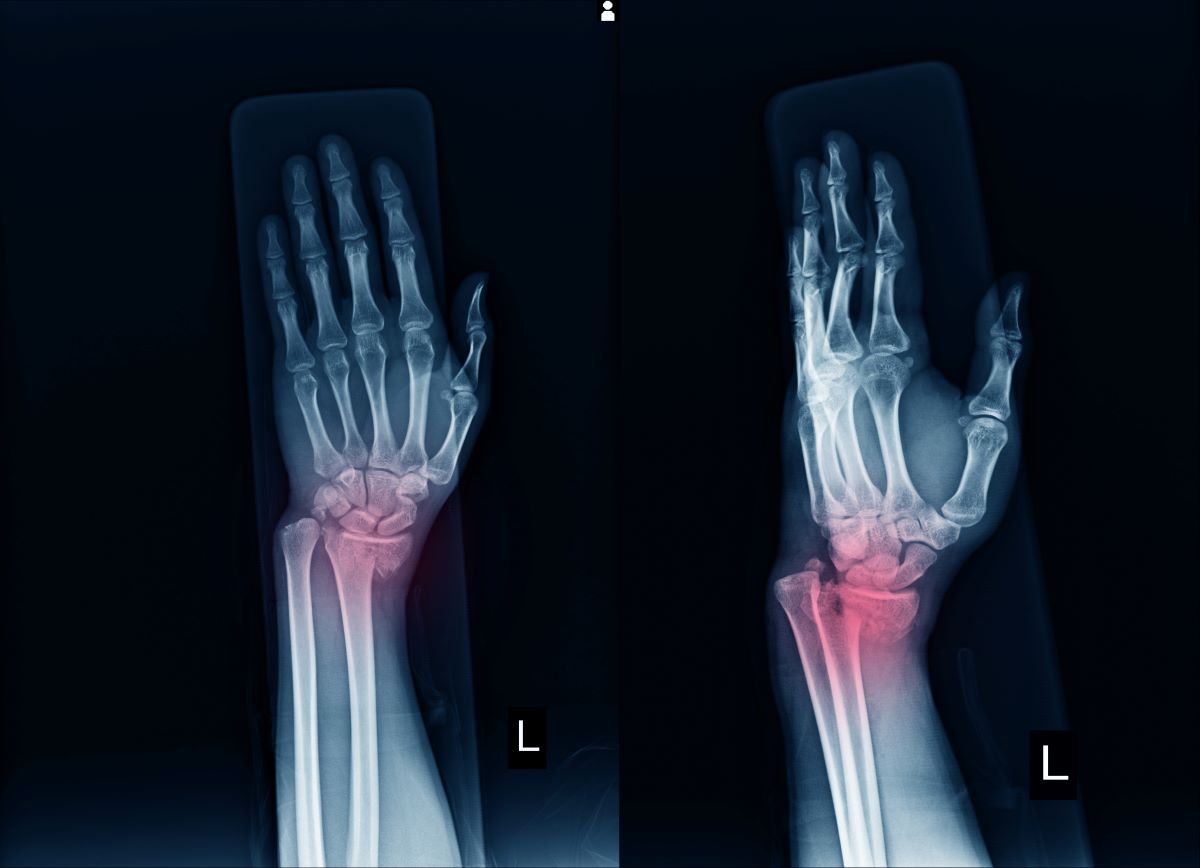

From www.vecteezy.com

film x ray wrist show fracture distal radius forearm s bone 2465811 Pain In Forearm After Wrist Fracture Often, people break their wrists trying to catch. If you suffered the wrist break due to the onset of osteoporosis, take some. A broken wrist, or wrist fracture, typically causes immediate swelling, pain, and tenderness. If you have a broken wrist, you will probably need a cast, splint or sling. A broken wrist, or wrist fracture, is a common injury. Pain In Forearm After Wrist Fracture.